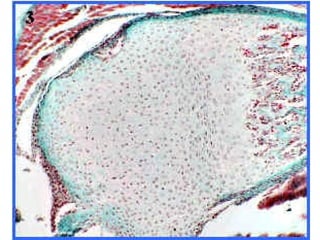

 formar placas o láminas relativamente sólidas,

caracterizadas por una gran resistencia a la

compresión: TEJIDOS CARTILAGINOSOS

Tejido cartilaginoso

 formar placaso láminas relativamente sólidas, caracterizadas por una gran resistencia a la compresión: TEJIDOS CARTILAGINOSOS